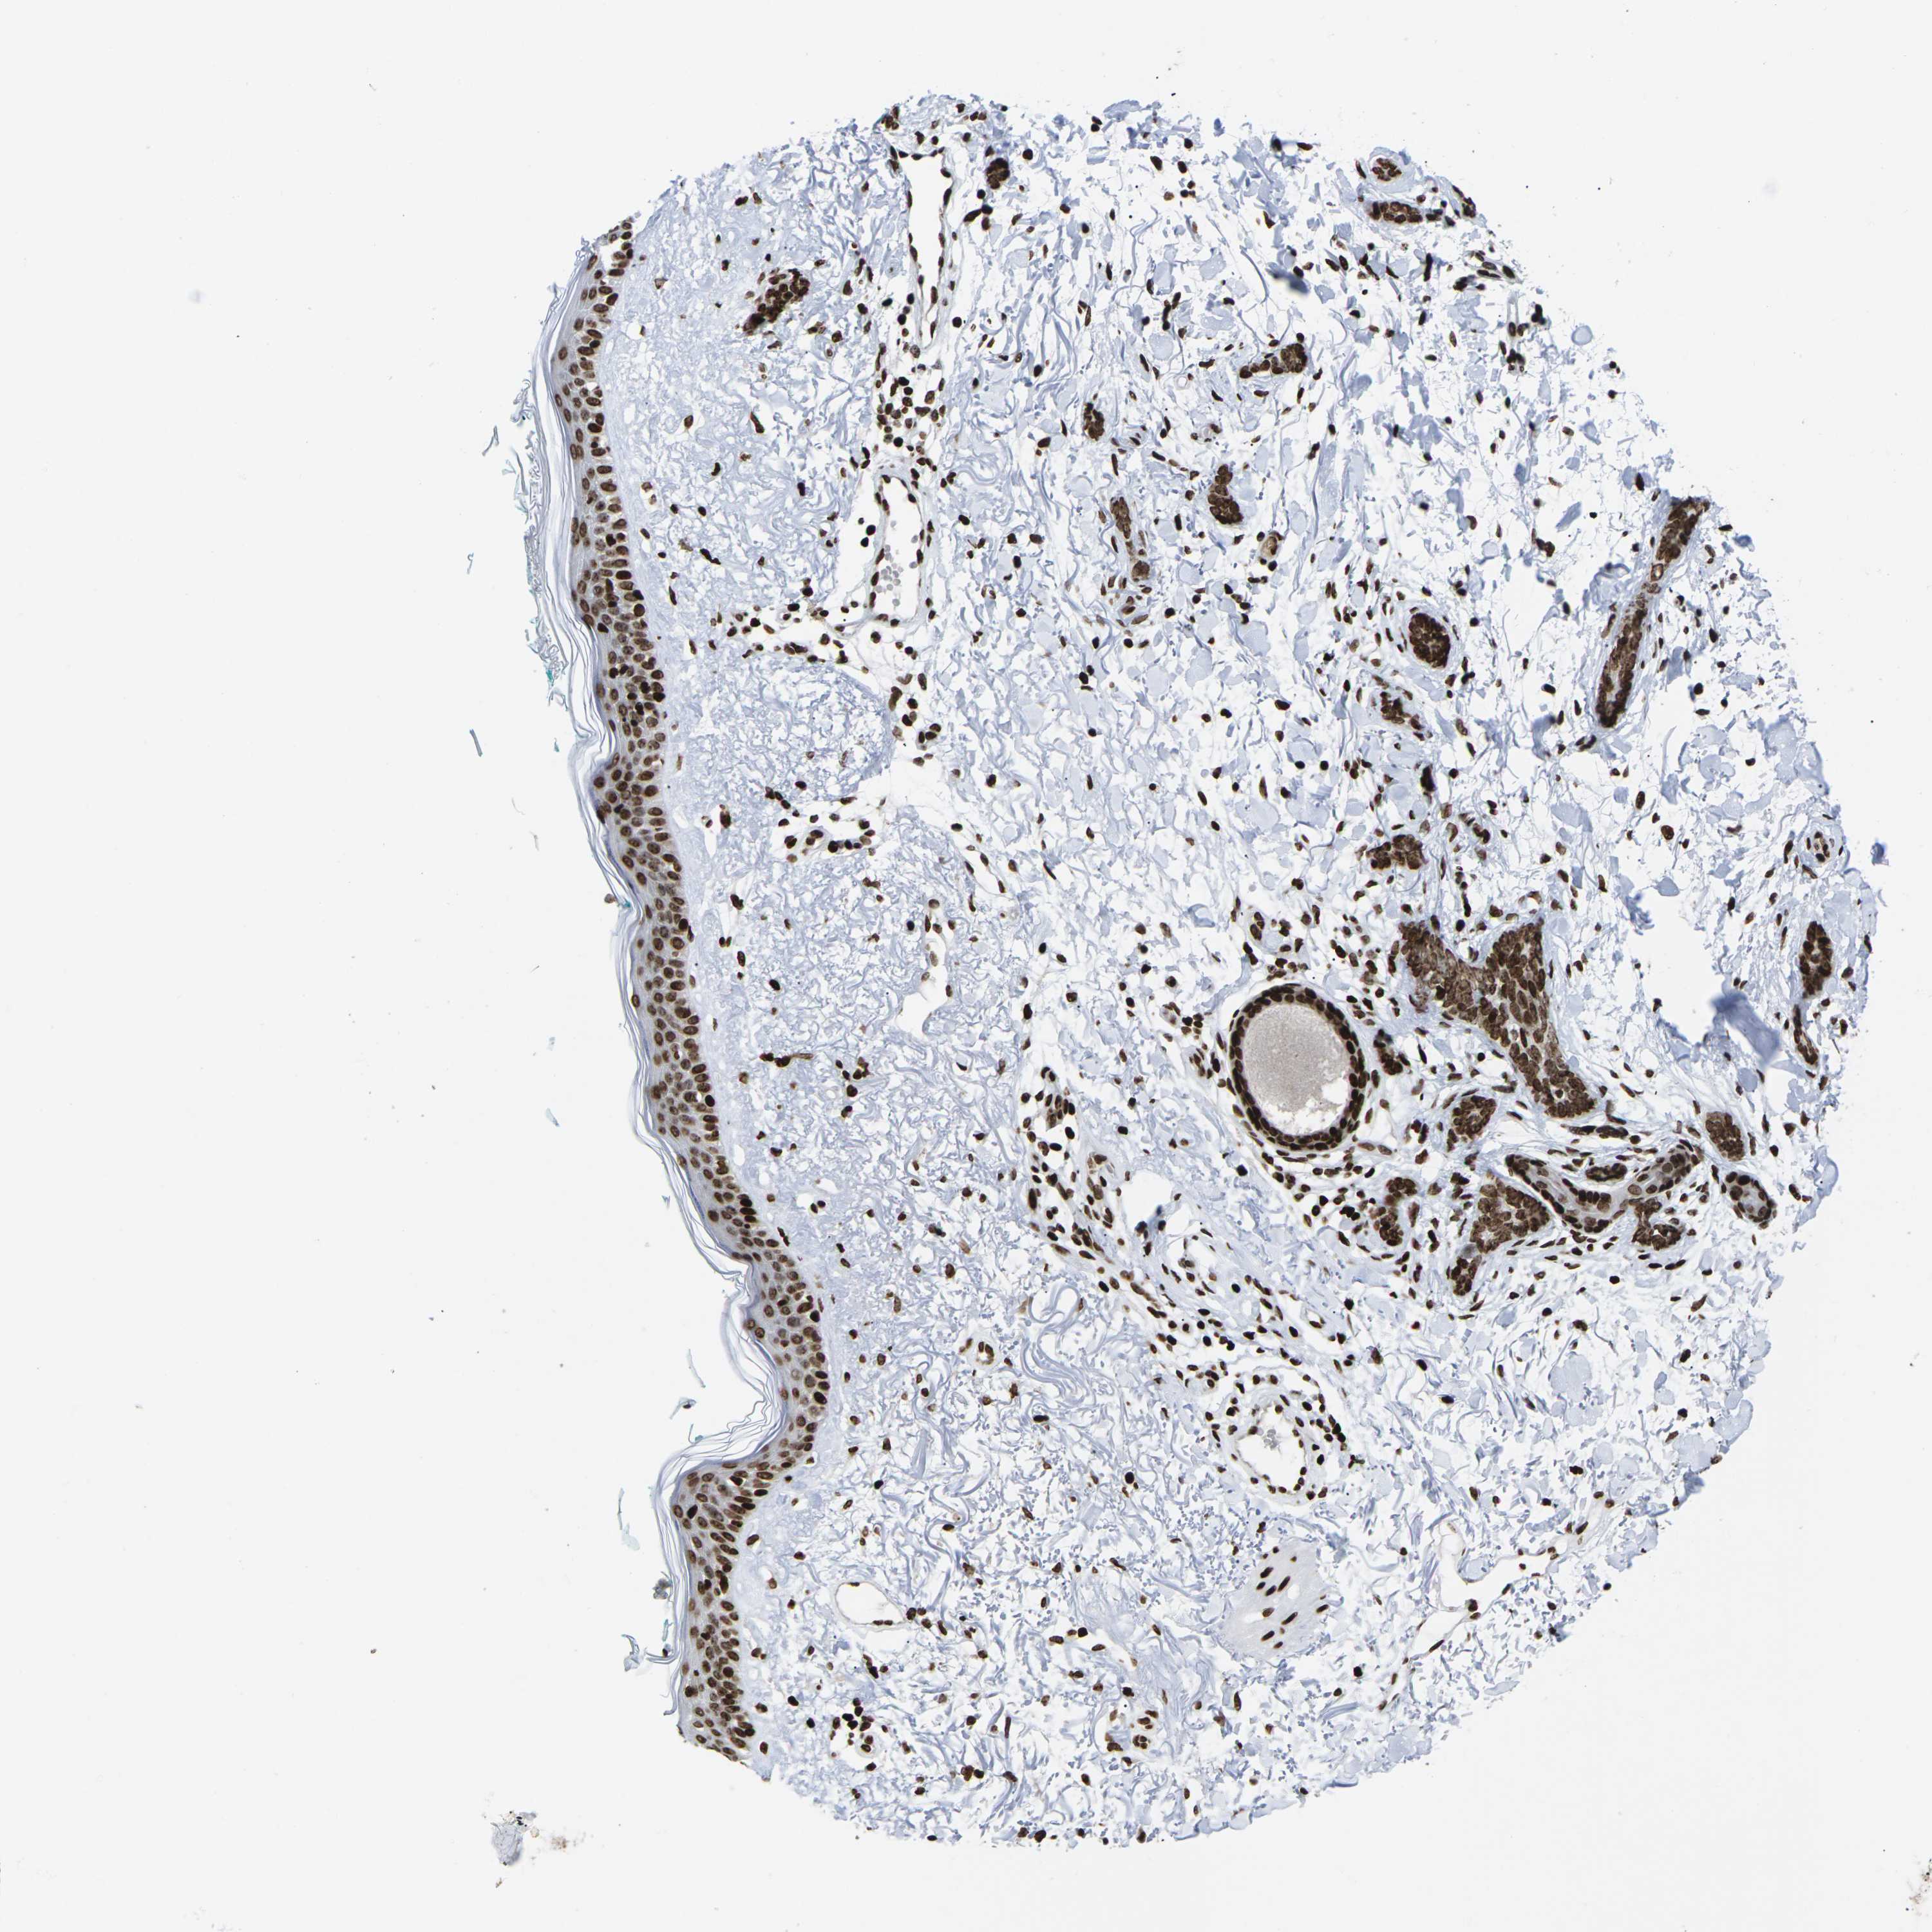

SKIN CANCER - Protein expressioni

A mouse-over function shows sample information and annotation data. Click on an image to view it in a full screen mode. Samples can be filtered based on level of antibody staining by selecting one or several of the following categories: high, medium, low and not detected. The assay and annotation is described here.

Each image is clickable and will lead to virtual microscopy that enables deeper exploration of all samples and also displays staining intensity scores, fraction scores and subcellular localization as well as patient and tissue information for each sample.

Antibody HPA055907

Squamous cell carcinoma in situ, NOS